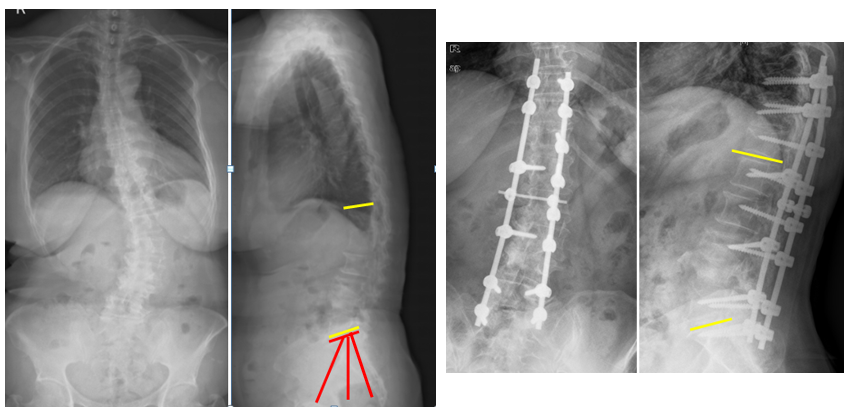

(2)上固定椎在交界区或存在交界性后凸

图6 长节段融合固定上固定椎(UIV)选择在胸10-12胸腰椎交界区是PJK的风险因素之一

T10骨盆固定,出现交界性后凸

行翻修手术:T9/10SP截骨,延长到T4固定,预防性双侧肋骨固定(VEPTR)

图32-33 肋骨固定